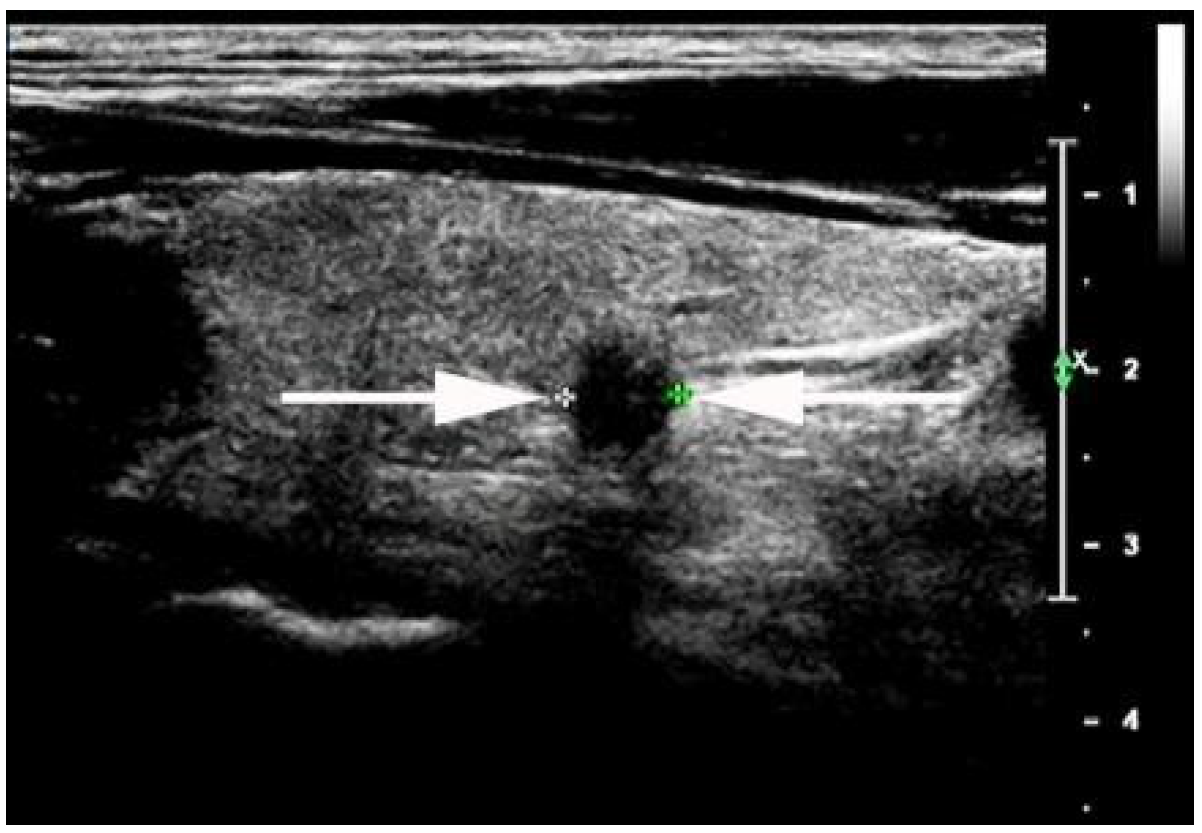

- Kwak, J.Y.; Kim, E.-K.; Youk, J.H.; Kim, M.J.; Son, E.J.; Choi, S.H.; Oh, K.K. Extrathyroid Extension of Well-Differentiated Papillary Thyroid Microcarcinoma on US. Thyroid 2008, 18, 609–614. [Google Scholar] [CrossRef]

- Moon, S.J.; Kim, D.W.; Kim, S.J.; Ha, T.K.; Park, H.K.; Jung, S.J. Ultrasound assessment of degrees of extrathyroidal extension in papillary thyroid microcarcinoma. Endocr Pract. 2014, 20, 1037–1043. [Google Scholar] [CrossRef]

- Chung, S.R.; Baek, J.H.; Choi, Y.J.; Sung, T.Y.; Song, D.E.; Kim, T.Y.; Lee, J.H. Sonographic Assessment of the Extent of Extrathyroidal Extension in Thyroid Cancer. Korean J. Radiol. 2020, 21, 1187–1195. [Google Scholar] [CrossRef]

- Ramundo, V.; Di Gioia, C.R.T.; Falcone, R.; Lamartina, L.; Biffoni, M.; Giacomelli, L.; Filetti, S.; Durante, C.; Grani, G. Diagnostic Performance of Neck Ultrasonography in the Preoperative Evaluation for Extrathyroidal Extension of Suspicious Thyroid Nodules. World J. Surg. 2020, 44, 2669–2674. [Google Scholar] [CrossRef] [PubMed]

- Jeong, S.Y.; Chung, S.R.; Baek, J.H.; Choi, Y.J.; Sung, T.-Y.; Song, D.E.; Kim, T.Y. Sonographic assessment of minor extrathyroidal extension of papillary thyroid micro-carcinoma involving the posterior thyroid capsule. Eur. Radiol. 2022, 32, 6090–6096. [Google Scholar] [CrossRef] [PubMed]

| STCS (n) | 37 | 17 | 0.0002 |

| Anterior capsule involved (n) | 15 | 7 | 0.018 |

| Posterior capsule involved (n) | 22 | 10 | 0.004 |